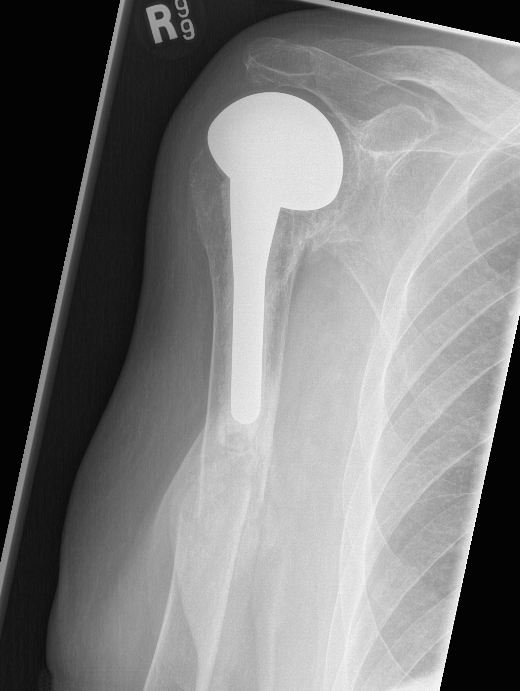

TSR Periprosthetic FractureTSR Periprosthetic Fracture

B.  ORIF

- displaced tuberosity fractures

- well-fixed prosthesis and fracture distal to prosthesis

Anterolateral approach and plate

C.  Revision

- loose humeral prosthesis / osteolysis

Long stem > 2 cortical diameters past fracture

aTSA fracture 1aTSA fracture 2revTSA following fracturerevTSA for fracture